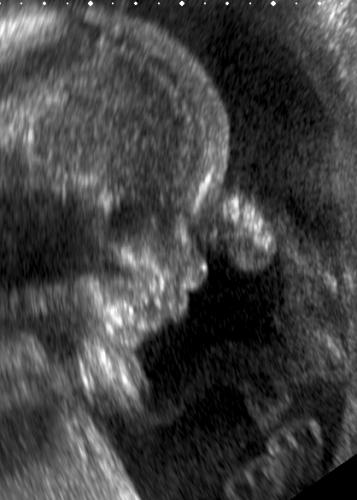

bon, piapias a sa petite tête ailleurs ces jours-ci donc ce blog ressemble un peu à... moui, n'importe quoi. déjà il fait un jour l'été un jour novembre donc je sais pas vous mais moi c'est le genre de truc qui me complique salement la journée. que la fille qui n'a jamais passé un mercredi en short sous une pluie de pôle se lève ou se taise à jamais. bien. ensuite, ce truc ballot: je vais sans doute me transformer en femelle hippopotame ces prochains mois et on ne flambe pas à toutes les caisses lorsqu'on sait qu'on va passer par toutes les tailles du 36 au 46 (bien sûr, écrire ce chiffre satanique me file des sueurs froides, qu'est-ce que vous croyez?) dans un futur proche. il y a des filles qui mettent leur slim jusqu'au 7e mois mais il y a aussi des gens qui ont vu la vierge. en ce qui me concerne, ma transformation de petit format en buveur de bière allemand est déjà spectaculairement enclenchée: j'ai un mari qui fait le mariole mais qui roule des yeux affolés en voyant à quel point mon profil est en train de muter en celui de depardieu en phase no cocaïne, cassoulet yes.

ava, cette vieille adolescente sur le retour, cette langue de vipère qui persifle sur le dos d'amandine avec sa bande de ragondins ricanneurs (ça ne va pas prendre avec nous, le "torrent de sensualité" de tournefeuille), est donc comme qui dirait sur la touche de la fashion. elle garde le sac de sa copine. avec quoi comme perspectives devant? eh bien d'insolubles bidules. et je ne parle pas forcément du jour où je trouverai mon locataire en train de brûler des bagnoles avec les racaillets du quartier. juste du fait de trouver des vêtements à porter dans ma vie sociale. car bien sûr on peut aller nu: mais on a sa pudeur, madame. et puis l'interview à poil ça ne va que pour paris dernière. c'est peu dire que le partouzard parisien est peu mon client quotidien.

femmes dignes de ce nom qui êtes passés par là et dont les entrailles sont bénies, quel était votre secret pour ne pas ressembler à des vaches enceintes de retour d'un shopping chez gemo? faudra-t-il nécessairement en passer par les leggings et le t-shirt "bébé à bord"? la salopette de coluche et la robe façon "sous cette housse, notre gros cadeau mystère"? faut-il se résoudre à claquer 2000 euros ds un jean de grossesse? peut-on se trimballer en micro-jupette avec le bide de carlos? une femme enceinte a-t-elle droit à sa dose de sexyness?